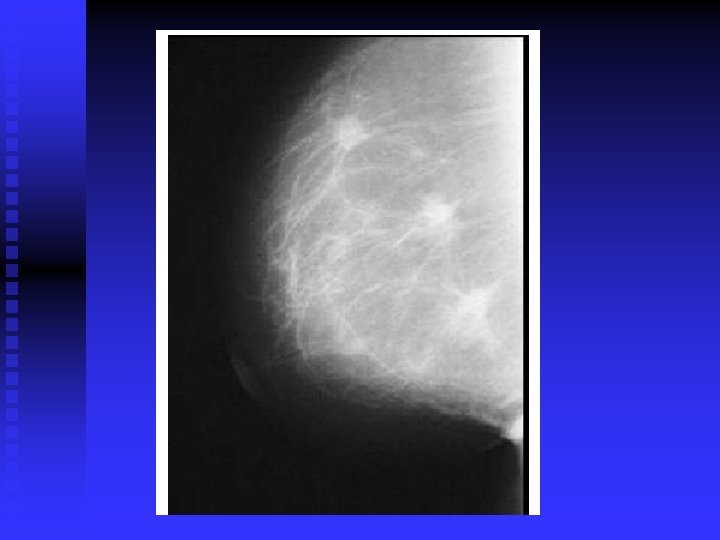

42 -year-old woman with fibrocystic condition